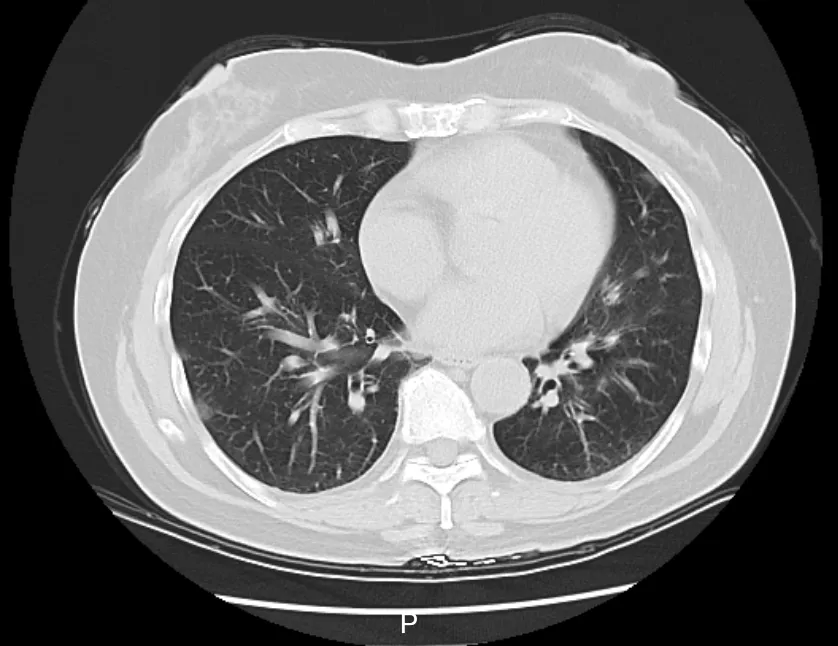

接诊的庞医生了解到,李阿姨在当地接受了一些治疗,但体温仍居高不下。家中同行的6个人,有5个人都先后发烧了。庞医生判断,李阿姨大概率是得了传染性较强的呼吸道疾病,立即给她安排了血常规、相关病毒抗原检测,以及更清晰的肺部CT检查,以便进一步了解病情。

△李阿姨肺部CT影像

检测结果显示,李阿姨已经得了病毒性肺炎,甲型流感病毒核酸呈阳性。这一下,罪魁祸首找到了,是甲流搞砸了这一家人一次本该圆满的旅行。

发热门诊医生立即给她用上了玛巴洛沙韦抗病毒。不出2天,李阿姨的体温恢复了正常,咳嗽咽痛等症状也有了明显好转。